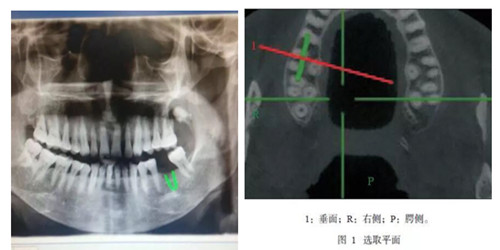

CBCT是一種錐形束投照計(jì)算機(jī)重組斷層影像設(shè)備,可用于種植、頜面外科、正畸、牙體牙髓病、牙周病等方面的檢查。通過口腔CT的立體影像可以全面了解頜骨形態(tài)、牙齒周圍的解剖結(jié)構(gòu),牙根的位置與形態(tài)、下頜神經(jīng)管的走向和范圍、上頜竇底的位置及上牙牙根與上頜竇的關(guān)系、下牙牙根與下頜神經(jīng)管的位置關(guān)系等肉眼不可見的組織結(jié)構(gòu)。

CBCT具有特點(diǎn):圖像分辨清晰、重建速度快速、重建時(shí)間低于15S,成像范圍合理、偽影校正技術(shù)獨(dú)特,避免重疊等,操作簡單便捷,一次掃描即可獲得全口腔雙牙列三維立體影像 等一系列特點(diǎn)。與傳統(tǒng)CT相比CBCT的輻射量更低、牙齒與頜骨成像更加清晰。我院CBCT附送患者一張影像刻錄光盤,觀看膠片不需要觀片燈,直接在醫(yī)生電腦上即可動(dòng)態(tài)觀看圖像;消除患者等待煩惱。